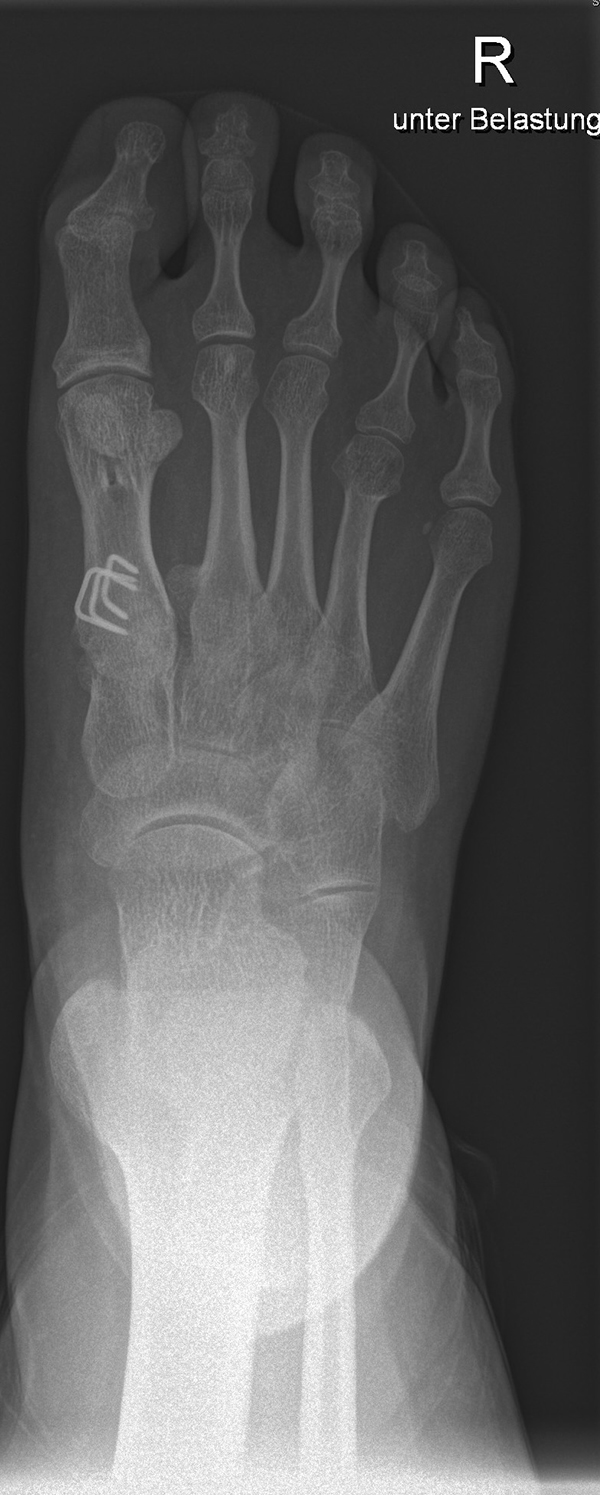

In der Regel bestehen aktive Wachstumsfugen bei Mädchen bis zum 12. und bei Jungen bis zum 14. Lebensjahr, mit Abweichungen von einem Jahr nach unten und nach oben. Präzise Informationen unter anderem darüber gibt das präoperative Röntgenbild (Abb. 2).

Abb. 2 a-c: offene Wachstumsfugen MT I Basis und Zehen (a), teilweise geöffnete Wachstumsfugen (b) und geschlossene Wachstumsfugen (c).

Damit die minimalinvasive Fußchirurgie zur Korrektur kindlicher oder jugendlicher Fußdeformitäten erfolgreich angewendet werden kann, erfordert die präoperative Diagnostik Röntgenbilder in drei Ebenen am stehenden Fuß. Röntgenbilder ohne Belastung des Fußes sind nicht zielführend. Im Fall von schweren Rückfußdeformitäten wird das obere Sprunggelenk in die radiologische Diagnostik mit einbezogen in Kombination mit der Rückfußaufnahme unter Belastung („Saltzman View“). Das OSG wird in zwei Ebenen geröntgt. Die streng seitliche Aufnahme des OSG kann bei den komplexen Fußdeformitäten mit der seitlichen Aufnahme des Fußes unter Belastung kombiniert werden. Das reduziert die diagnostische Strahlenbelastung der Kinder.